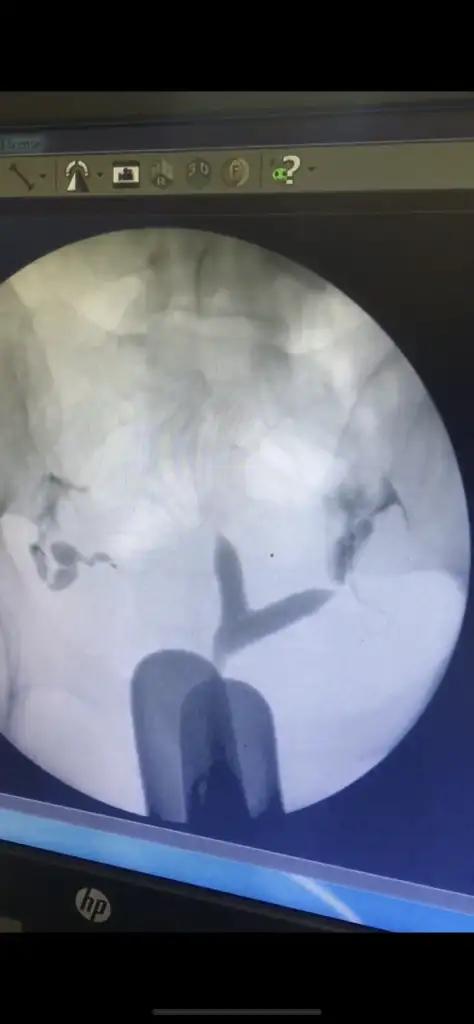

Benimki bu şekildeYok canım elimde cd si var bildiğin Y şeklindeydi benimki. Rahim ağzına kadardı perde. Banada gerek yok düşük olursa yaparız dediler ama neden düşük olmasını bekleyeyim varsa bir sıkıntı olayım hemen dedim. İyi ki olmuşum. Baya kötü bir haldeymiş. Hatta biraz kaldı perde daha fazla ileri gidemedi.

Oooo canım kesinlikle yaptırmalısın baya perde varBenimki bu şekilde